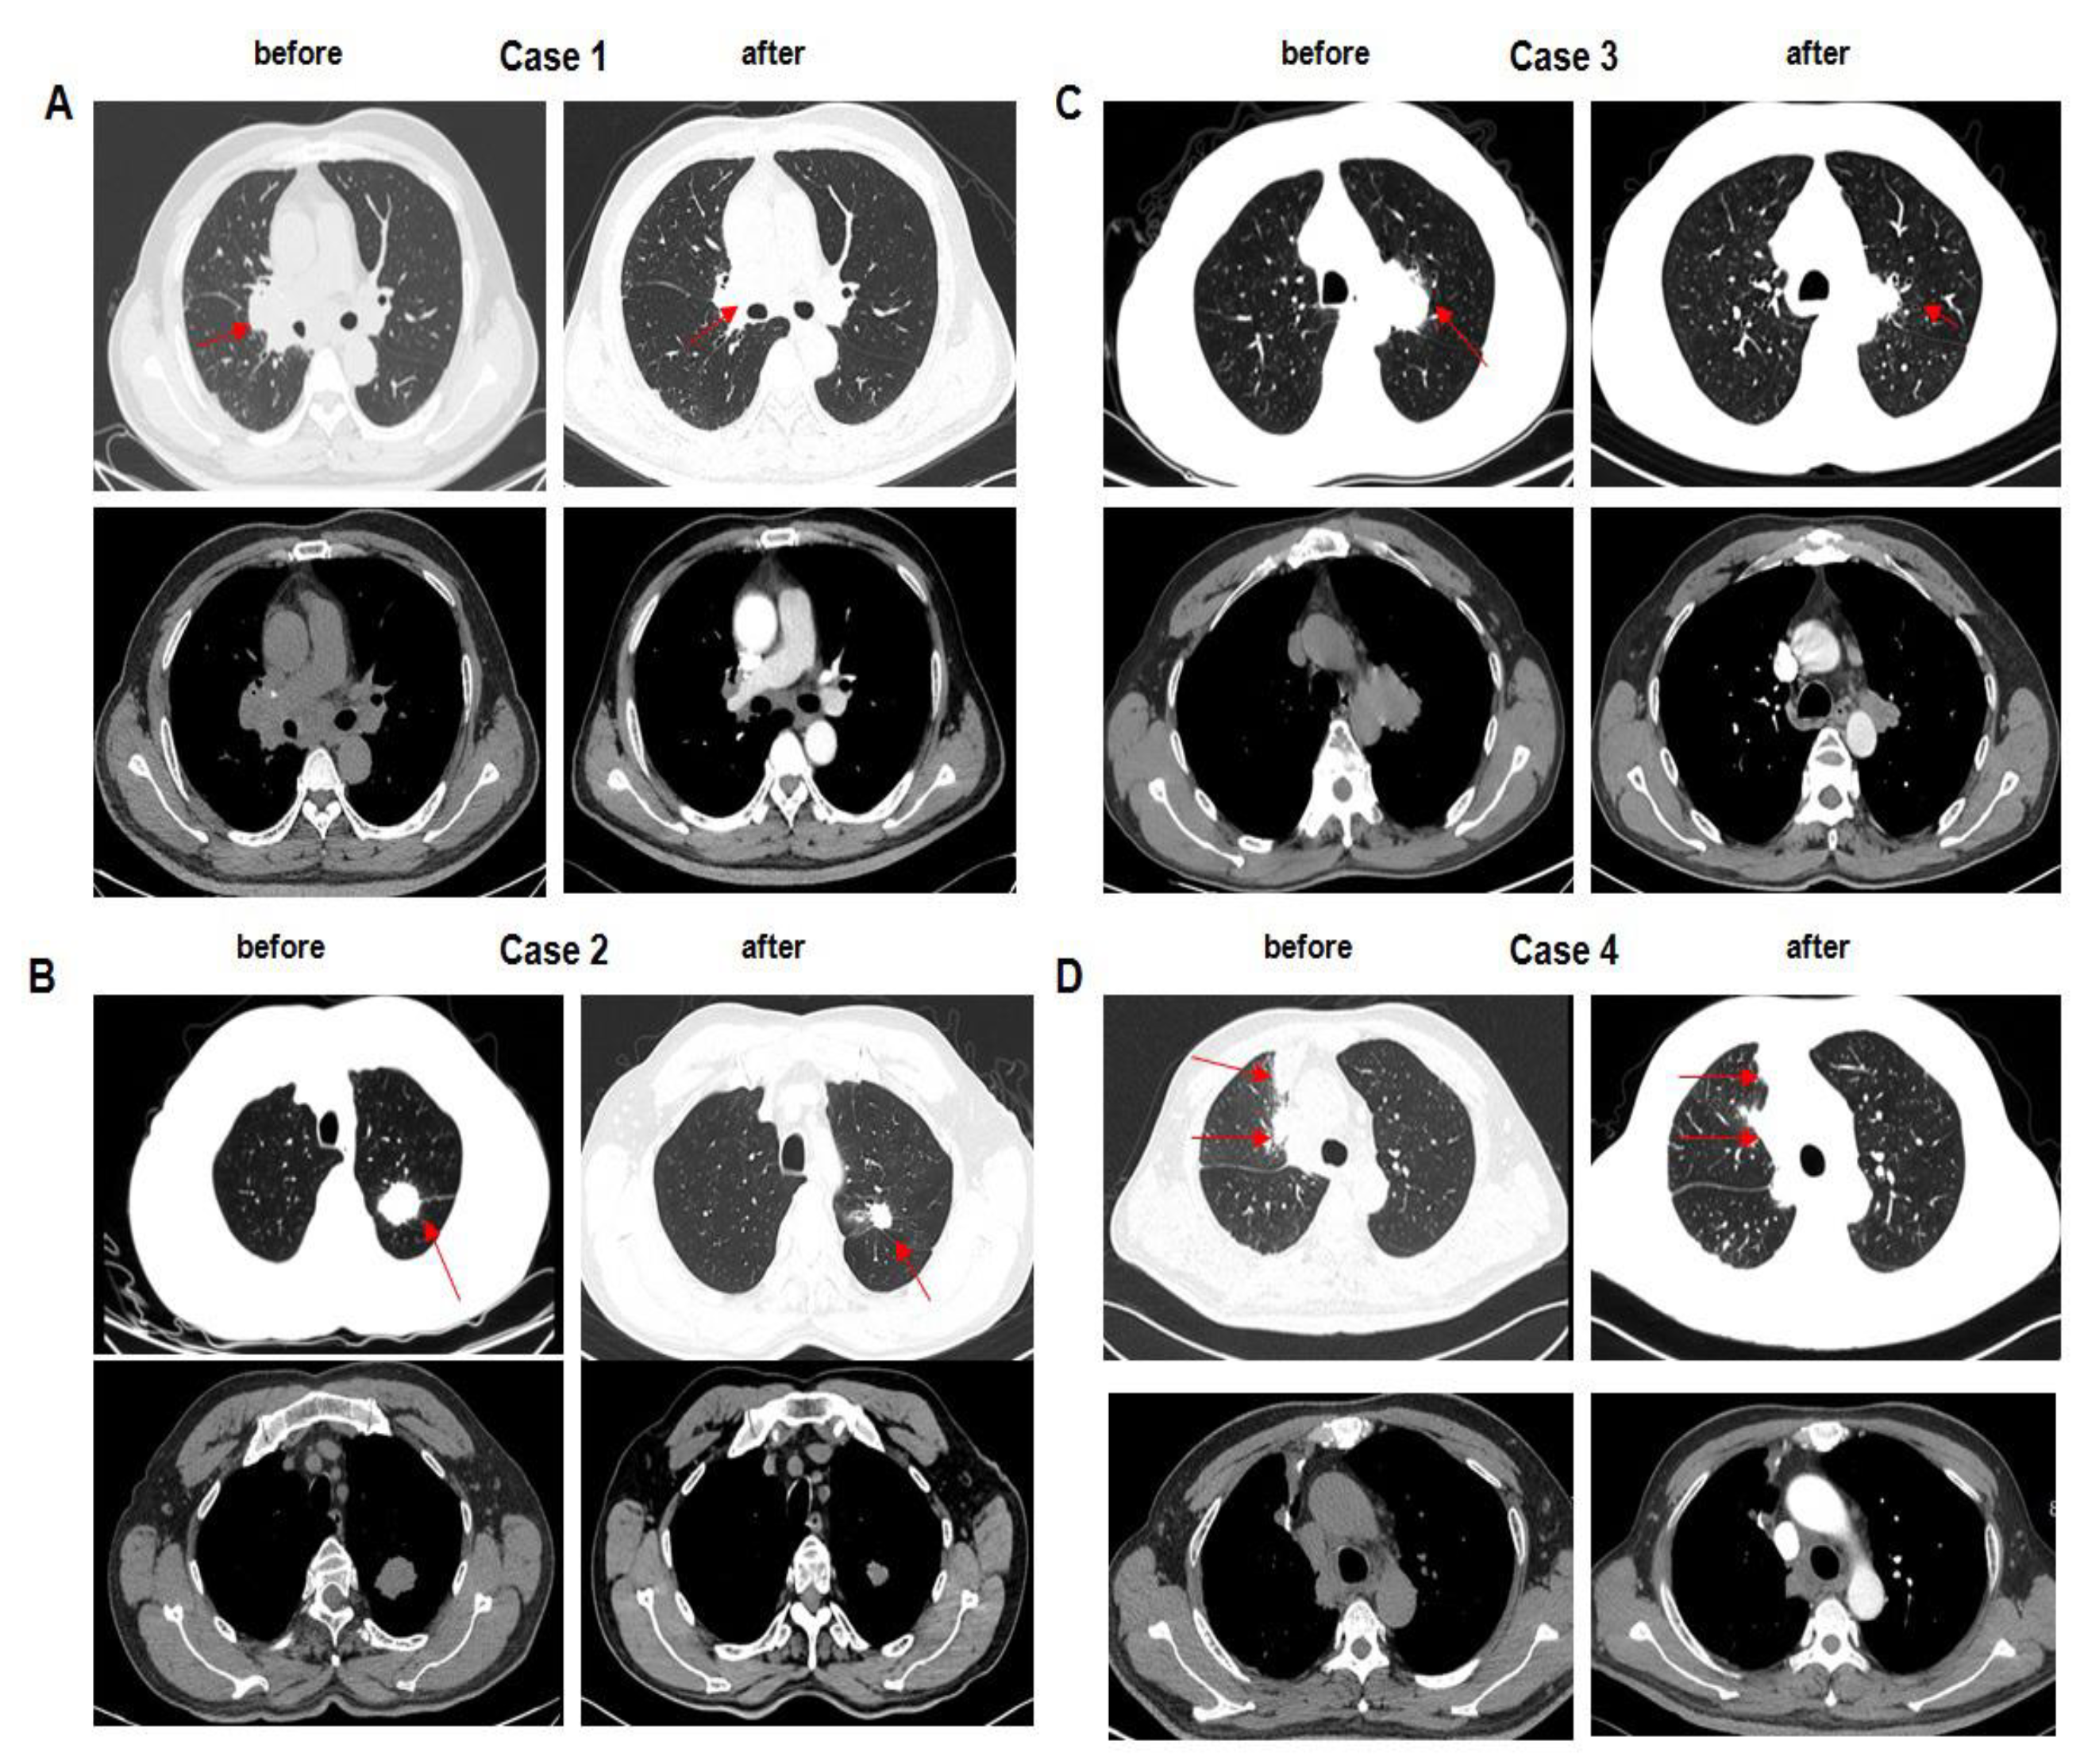

3.3. Validity

3.4. Biomarkers